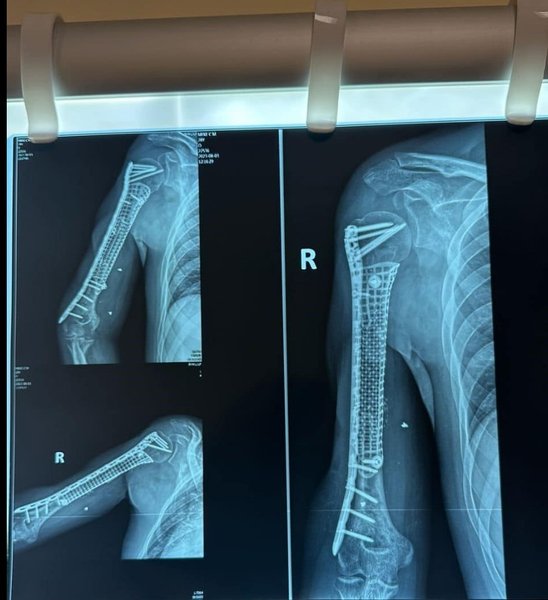

Для протезирования кости врачи начали использовать индивидуальные титановые импланты, изготовленные с помощью 3D-технологий. Благодаря этому удается при сверхсложных ранениях спасти конечности.

В сообщении вспомнили, как в больницу привезли морского пехотинца с тяжелым ранением плеча. У него не было части кости, вырван большой участок мышц, но сохранен сустав. Бойцу повезло, поскольку на предыдущих этапах лечения специалисты не ампутировали руку. Ранее врачи со спины переместили мышцы с кожей на плечо. Впоследствии хирургам удалось установить имплант. После операции воин через три месяца уже мог неплохо двигать рукой, что подтвердило эффективность применения такой методики.

Процесс изготовления индивидуального титанового импланта специалисты называют длительным и довольно кропотливым. Сначала хирург отправляет техническое задание инженерам-волонтерам компании Materialise. Они создают 3D-модель, а затем — макет. Далее медик вносит свои замечания, учитывая конкретную ситуацию пациента. Впоследствии печатается имплант из титана, ведь именно этот металл лучше всего инсталлируется в кость.